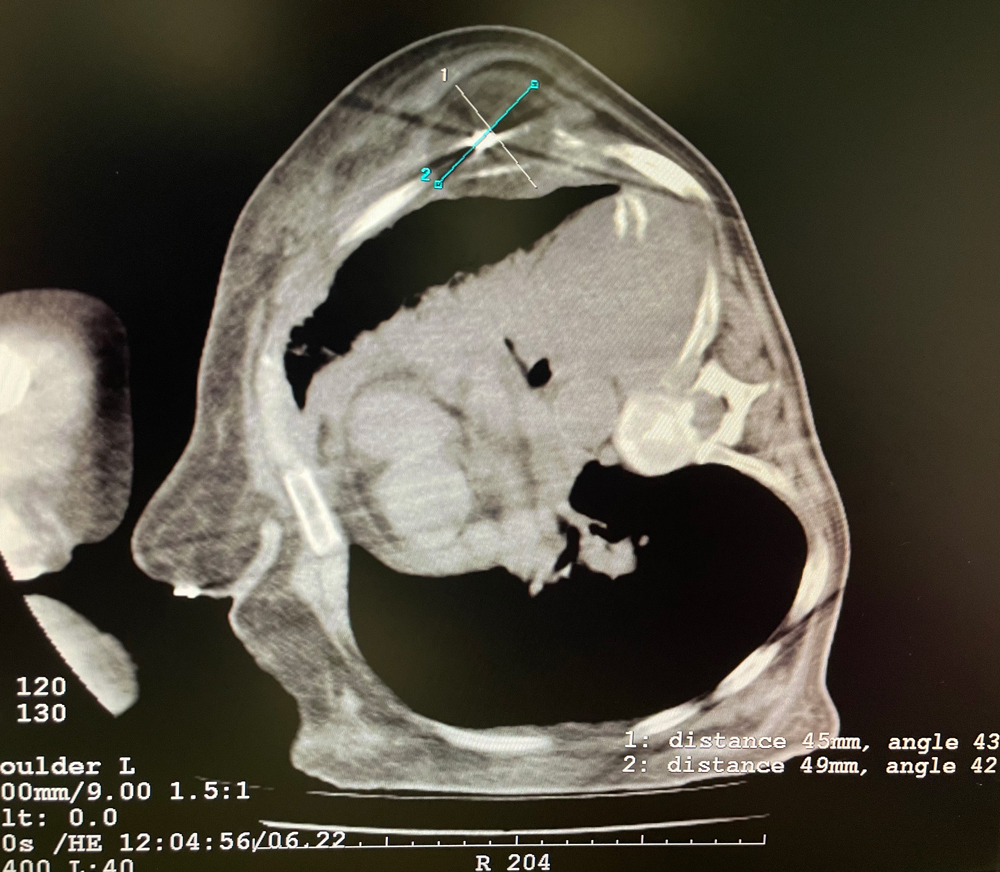

女,56歲,肺轉(zhuǎn)移瘤,骶骨、左側(cè)肋骨各一轉(zhuǎn)移灶,病灶大小均為5cm。骶骨轉(zhuǎn)移灶、肋骨轉(zhuǎn)移灶各進(jìn)行2個凍融循環(huán)。患者術(shù)后狀況良好。